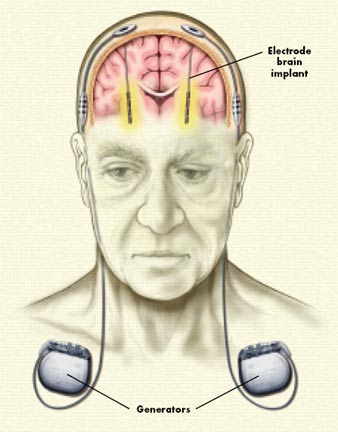

La ECP es una técnica quirúrgica usada para el tratamiento del temblor esencial y distonía espasmódica, consistente en la implantación de un electrodo tetrapolar en un núcleo que se activa mediante un generador de pulsos.

Una vez introducido el electrodo en la zona a tratar, se conecta con un generador que se implanta subcutáneamente, habitualmente en la zona clavicular, provocando una inhibición de las células diana, de forma que la técnica consiste en el estímulo de los circuitos neurales alterados en los ganglios basales, generando una inhibición mediante los impulsos eléctricos generados por el ECP (Gómez González, 2010).